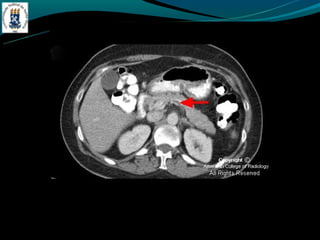

TROMBOSE DA VEIA PORTA

-Complicação de cirrose

-Invasão ou compressão tumoral

-Hipercoagulabilidade

-Inflamação

-Incidência de 5% na hipertensão portal e próximo de 30% no

CHC

-TC: Esplenomegalia, formação de colaterais, ascite, e pode ter

alta atenuação na fase arterial.

-RM: trombo agudo hiper em T1 e T2, crônico hipo em T1 e

hiper em T2.

TROMBOSE DA VEIAPORTA -Complicação de cirrose -Invasão ou compressão tumoral -Hipercoagulabilidade -Inflamação -Incidência de 5% na hipertensão portal e próximo de 30% no CHC -TC: Esplenomegalia, formação de colaterais, ascite, e pode ter alta atenuação na fase arterial. -RM: trombo agudo hiper em T1 e T2, crônico hipo em T1 e hiper em T2.